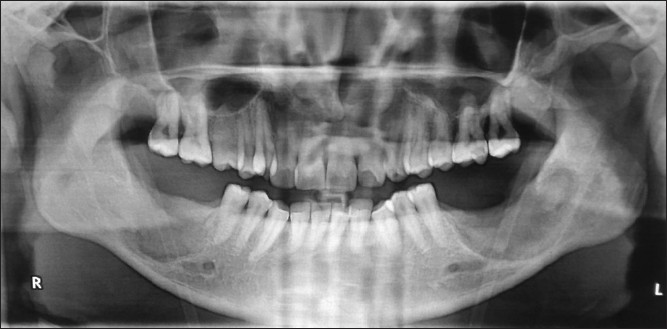

A radiographic investigation by CT scan revealed a unilocular well-defined corticated hypodense lesion involving impacted mandibular third molars bilaterally [Figure 3]. The dimensions of the hypodensities were 31 and 42 mm anteroposteriorly on the right and left, respectively. There were also associated supernumerary teeth on both sides. The supernumerary teeth were small in size than third molars with single conical root and were placed coronally in close relation to third molars on both sides. The hypodensities were associated with radicular resorption of the first and second molars. Radiographs also revealed the inferior displacement of the mandibular canal. Incidentally another bilateral hypodense lesion associated with the crowns of maxillary third molars was observed. CT-Scan revealed a well-defined and corticated margin was observed surrounding the unilocular hypodensity. In maxilla, CT-scan revealed the dimensions of hypodensities around the crowns of third molars to be 15 and 18 mm in diameter on the right and left side, respectively [Figure 4] and [Figure 5]. There was no root resorption of adjacent teeth observed in maxilla. In all four quadrants the hypodense lesions were attached to the cementoenamel junction of the third molars at an acute angle which is one of the classical radiographic finding in cases of dentigerous cyst. Coronal sections and three-dimensional CT revealed bilateral lingual and buccal cortical perforations in mandible [Figure 6]. On aspiration a straw-colored fluid was obtained from each of these cystic lesions which is diagnostic of a dentigerous cyst [Figure 7]. | Figure 3: CT image showing bilateral expansile radiolucent lesion surrounding both the mandibular and maxillary third molar regions along with supernumerary teeth

Click here to view |

It is important to perform radiological examination for unerupted teeth in which panoramic radiograph may be used primarily. However, in extensive lesions, CT scan is considered as the gold standard. Thus in this case a CT scan was chosen as a radiological investigation of choice. Radiographic evaluations of dentigerous cysts are classically seen as radiolucent shadows associated with unerupted teeth and seemingly attached to the cementoenamel junction. [18] CT scan imaging gives information about the origin, size, content, cortical plate thickness, and relationship of the lesion to adjacent anatomical structures. [19] CT could be beneficial to determine whether roots of the adjacent teeth were located within the radiolucent space or not associated with the lesion. [20] According to the location of radiolucency around the crown of an unerupted tooth, there are three main types of dentigerous cyst; they are central, lateral, and circumferential type. It becomes important to differentiate between the dentigerous cyst and other unilocular radiolucent lesions presenting in the third molar region. Keratocystic odontogenic tumor appears as a less expansile radiolucent lesion and also the root resorption of adjacent teeth is rare as compared to dentigerous cyst. In this presented case the root resorption of adjacent teeth is seen on radiological investigation. Adenomatoid odontogenic tumor also shows similar features as dentigerous cyst; however, it is differentiated by the presence of intracystic radio-opaque structures. In younger patients, the periapical radiolucencies associated with deciduous teeth may mimic pericoronal radiolucencies of succeeding permanent teeth and may give a false impression of dentigerous cyst. Radiographs alone will not lead to a definitive diagnosis. The diagnosis can be confirmed only after histopathological investigation.